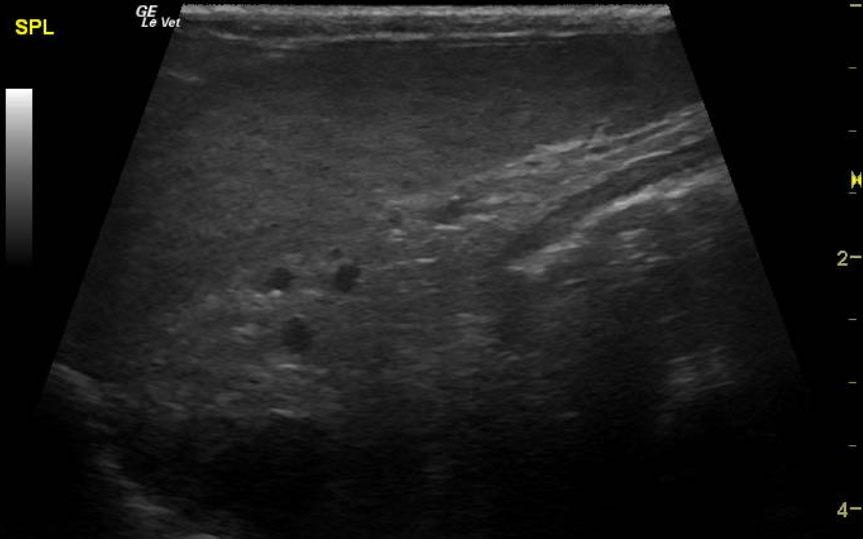

Image Interpretation

The spleen was enlarged and micronodular with slight scalloping contour. The spleen measured 1.33 cm. The mesenteric root lymph nodes were enlarged at 0.62 cm with reactive surrounding fat. Other mesenteric root lymph nodes measured 1.4 x 2.0 cm with reactive fat. Slight free fluid was noted owing to lymphatic strangulation. The remainder of the bowel revealed increased muscularis to mucosa thickening with a 2:1 ratio.